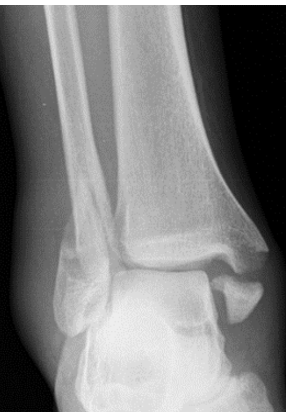

What type of fracture is this?

Pott

What is a pott fracture?

Complete fracture of distal fibula, may involve ligament damage and fracture of medial malleolus and distal tibia